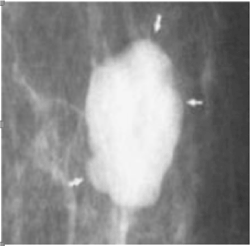

Two images of the form are exposed, more common in that is discovered the disease, from the point of view Imaging (Figures 1 and 2). At the onset of any of these signs, then imposes the realization of biopsy for a conclusive diagnosis. There are several methods to obtain the sample of tissue, which would definitively with the histological diagnosis of the patient in question [9,10].

Figure 2. Presence of macrocalcifications.